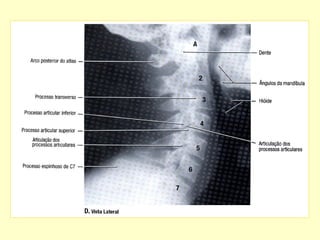

COLUNA CERVICAL PERFIL

Para avaliação da articulação

atlanto-axial por radiografias

convencionais. Realizar incidência

A. P. com boca aberta e perfil.

C – Vista Lateral

ANATOMIA RADIOLÓGICA CERVICAL

Anatomia radiológica